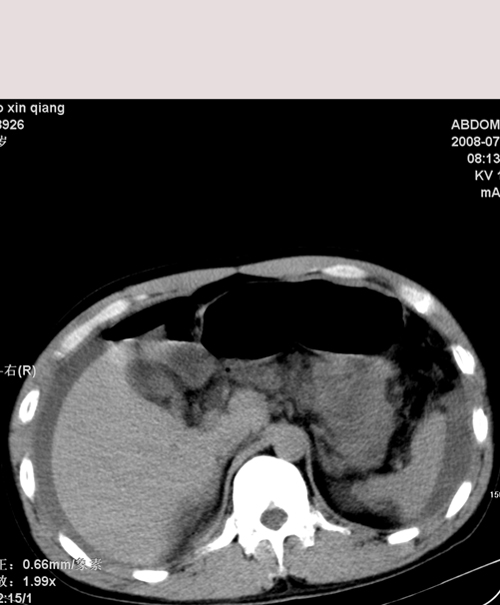

以下是引用随光逐影在2008-7-15 11:18:00的发言:[br]考虑为:1)腹部空腔脏器穿孔。2)右肾破裂并肾包膜下血肿,肾盂积血。3)腹水(血)。

以下是引用muzi888在2008-7-15 10:45:00的发言:[br]大量腹腔积液,气腹,肾皮质弧形高密度影,诊断;1 空腔脏器穿孔 2 右肾包膜下血肿

以下是引用yangyudong333在2008-7-15 12:06:00的发言:[br]考虑为:1)腹部空腔脏器穿孔。2)右肾破裂并肾包膜下血肿,肾盂积血。3)腹水(血)。